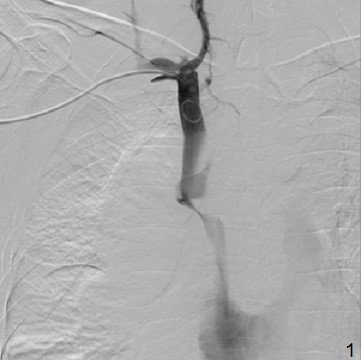

Səbəbin təyini

YBV sindromu təyin edildikdən sonra vacib məsələ səbəbin təyinidir. Əksər hallarda anamnez və KT səbəbi müəyyənləşdirməyə imkan verir (kateter, travma, tromboz, törəmə və s.). Lakin mediastinal törəmə tapıldıqda  onun təbiətini müəyyənləşdirmək üçün biopsiya lazım gələ bilər. Əvvəllər kəskin formalı YBV sindromunda diaqnozu dəqiqləşdirmə müddətində sıxılmanı azaltmaq və vəziyyəti yüngülləşdirmək üçün təcili olaraq radioterapiya aparılırdı. Lakin radioterapiya histologiyanı dəyişdirir. Ona görə də hazırda kəskin durğunluğu azaltmaq üçün venoz stentlərdən istifadə edilir (Şəkil 18).

Şəkil 18. Kavaqrafiya.  YBV-ya stentin qoyulması (1-2)